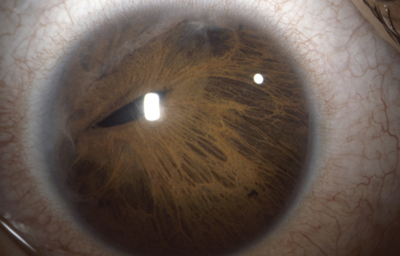

La Atrofia Esencial del Iris. Se produce cuando el endotelio anormal prolifera sobre la superficie del Iris, con subsecuente formación de una membrana contráctil que produce corectopia, atrofia del Iris y policoria falsa; si el endotelio anormal prolifera sobre el ángulo de la cámara anterior genera sinequias y glaucoma.

Atrofia Esencial del Iris - OD de paciente femenina de 36 años

Archivo fotográfico Dr. Carmen Barraquer